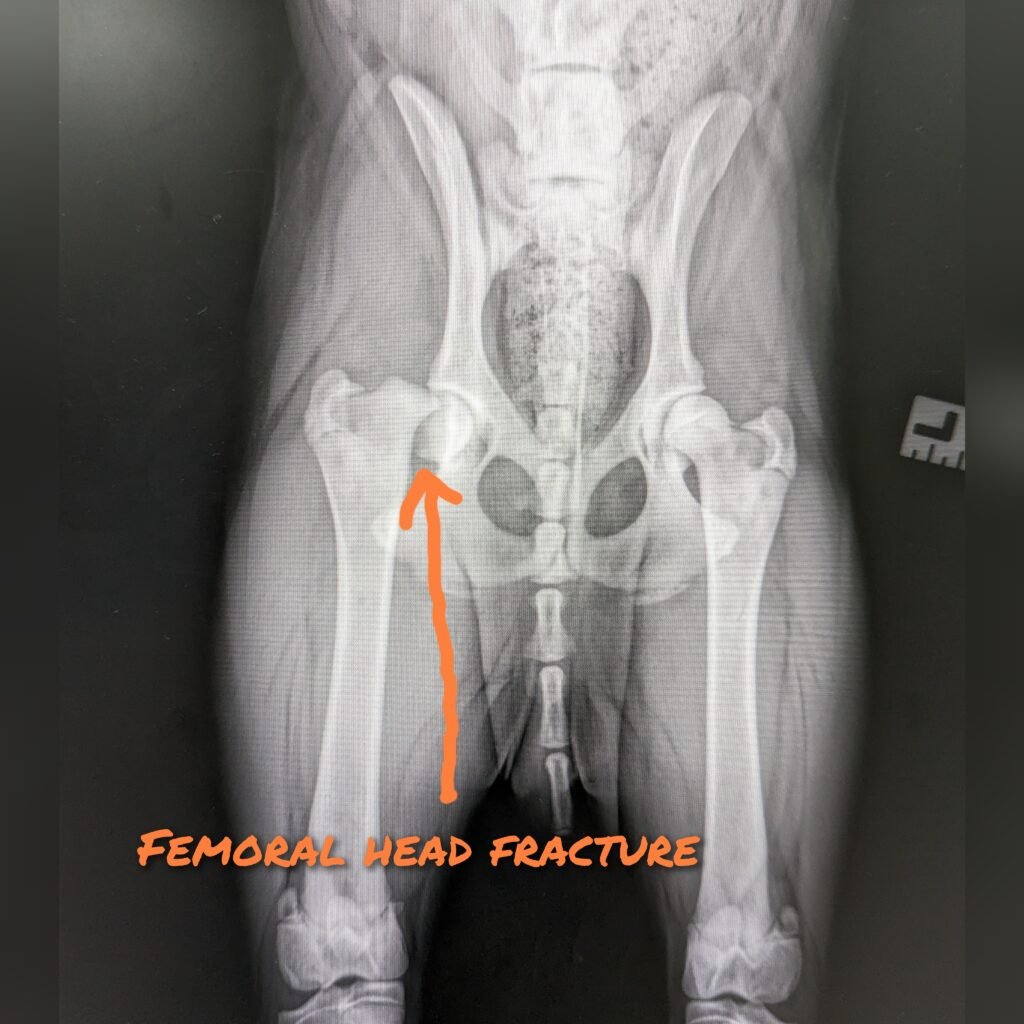

FHNE involves surgical removal of the femoral head and neck and it’s considered as salvage procedure because once the femoral head is removed, then it will be gone forever. This will prevent bone to bone rubbing within the hip hence eliminate pain and improve quality of life (QOL). The hip subsequently be stabilized with only the soft tissue (eg muscle/scar tissue). The prognosis is usually excellent for small size dogs and it usually costs less than other hip surgical procedure.